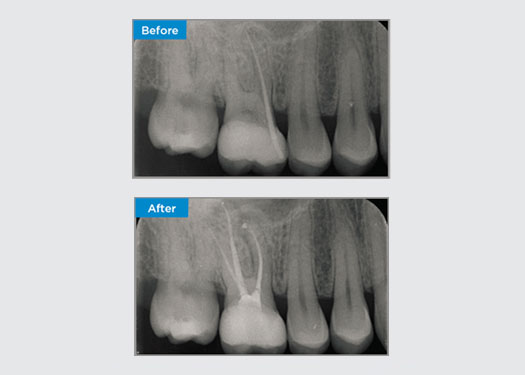

Paciente mujer de 35 años que acude tras derivación de un periodoncista especialista. Durante la evaluación endodóntica inicial, la paciente menciona que se realizó un alargamiento de la corona, previo a la colocación de la corona en el diente 16, dos años antes. Dos meses antes de que la paciente se presentara, había notado hinchazón de la encía palatina. El odontólogo general de la paciente había descubierto una bolsa periodontal de 7 mm adyacente al tracto del seno palatino asociado con el diente 16. La paciente fue derivada a un periodoncista especialista. El periodoncista especialista diagnosticó endodoncia primaria: lesión periodontal secundaria. La paciente tenía una higiene bucal satisfactoria y acudía regularmente al dentista. El diente 16 estaba sensible a la percusión. Se observó que los márgenes de la corona eran satisfactorios y que las bolsas periodontales alrededor del diente 16 tenían menos de 2 mm de profundidad en la cara vestibular. Sin embargo, en la superficie palatina, adyacente al tracto sinusal, había una bolsa periodontal aislada de 6,5 mm. La prueba térmica del diente 16 reveló una respuesta negativa. El diente 16 tenía factores de riesgo de periodontitis apical como respuesta negativa a las pruebas térmicas, dolor a la percusión, antecedentes de una restauración profunda después de una cirugía de alargamiento de la corona y enfermedad periapical identificable radiográficamente. El diente 16 no tenía antecedentes de dolor al morder o masticar, lo que puede indicar una grieta que comunica con la pulpa o los tejidos periodontales. La paciente no tenía factores de riesgo de enfermedad periodontal y no había bolsas anormalmente profundas alrededor de ningún otro diente.

Dr. Omar Ikram, endodoncista, Crows Nest, Nueva Gales del Sur, Australia